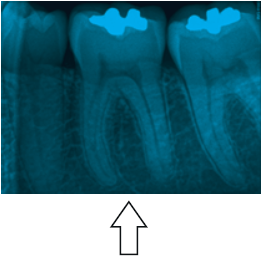

Analise a figura abaixo e assinale a alternativa correta:

Figura. Radiografia periapical

A seta aponta para a raiz mesial do 1º molar inferior que apresenta apenas um canal no centro da mesma

A forma de contorno inicial do dente apontado pela seta normalmente é triangular ou trapezoidal com a base voltada para a mesial